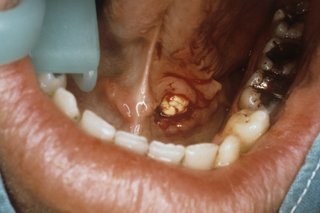

Większość kamieni pojawia się pod językiem w jednym z przewodów (gruczołów) dostarczających ślinę do ust. Nie zawsze możesz je zobaczyć.

Kamienie są białe i twarde

Kamień gruczołu ślinowego

Różnią się wielkością, ale większość z nich jest tak duża jak groszek